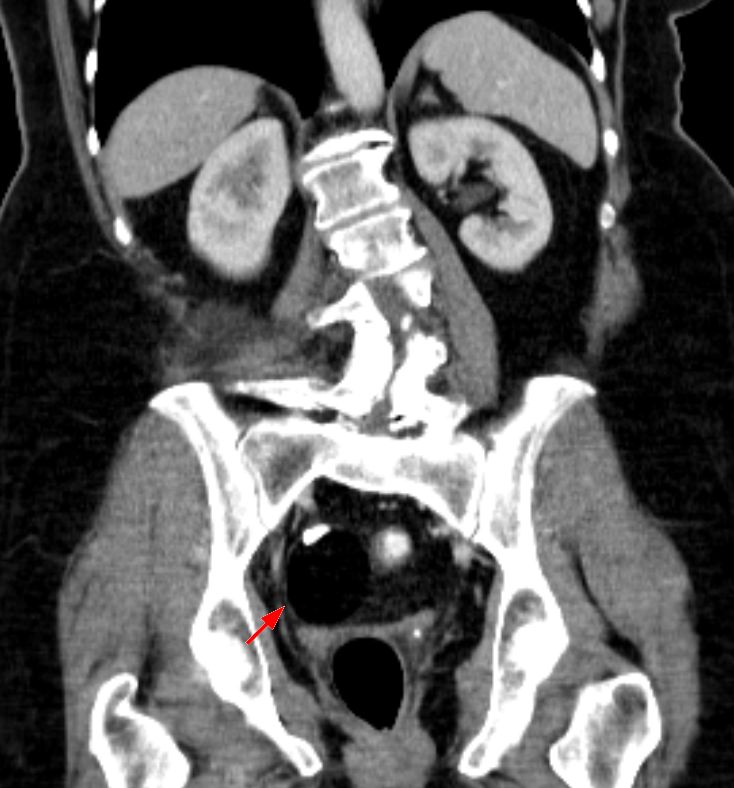

Pseudomyxoma Peritonei

Massive amounts of mucus in the peritoneum are a symptom of pseudomyxoma peritonei.

Appendiceal mucinous tumor that metastasize to the ovary frequently cause pseudomyxoma peritonei.